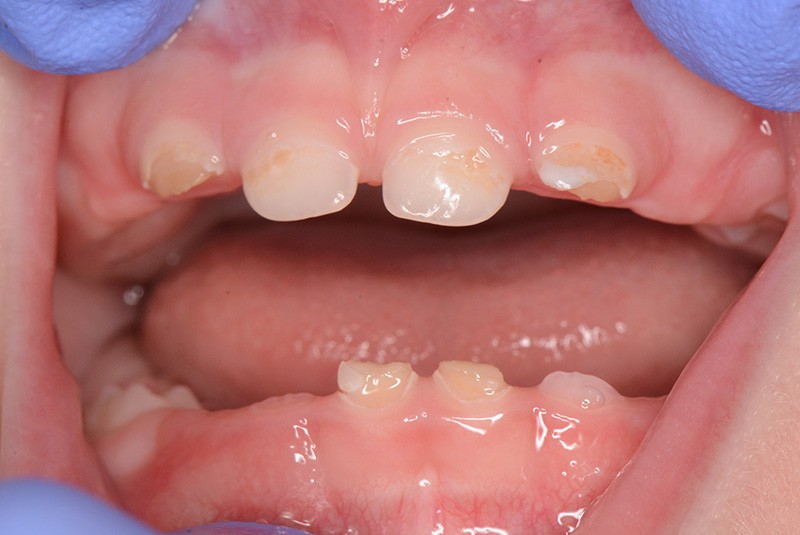

En France, la carie de la petite enfance (CPE) est souvent négligée chez l’enfant en denture temporaire, 24 % des dents temporaires affectées par des lésions carieuses cavitaires n’étant pas traitées, alors que la prévalence mondiale atteint 8,8 % [1]. Les enfants affectés ne sont souvent amenés en consultation que dans les cas sévères (tableau 1) lorsque les lésions nécessitent des réhabilitations prothétiques à envisager après correction du risque carieux (fig. 1).